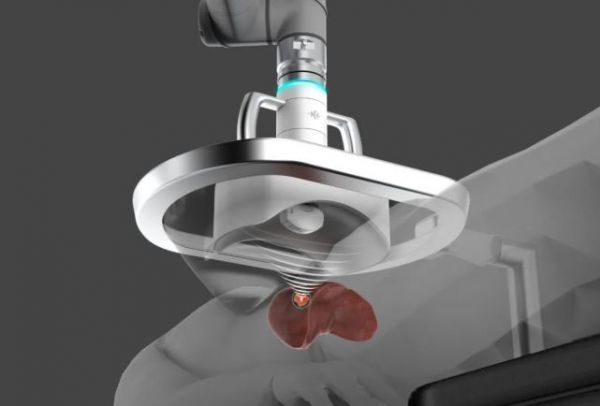

基于这一技术,HistoSonics公司开发了Edison无创超声手术机器人平台,这是第一个由实时成像引导的非侵入性、非电离和非热消融的超声手术平台。

HistoSonics将先进的机器人技术和成像技术与专有的传感技术相结合,提供了精确且可控的个性化无创超声治疗方案,也被称之为机器人辅助声波疗法(RAST SM)。

Edison平台是一个移动式的设备,能够在治疗室之间自由灵活的移动,它具有一个6自由度机械臂,机械臂含有一个治疗头和一个超声波换能器。

在Edison平台上,医生首先根据肿瘤的形状和大小来设计治疗方案。系统会告知医生创建气泡云所需的能量,从而定制个性化的治疗方案。治疗过程由医生实时监控,系统自动按照计划路径移动气泡云。

Edison的范围准确度可以达到um级,在焦点区域引起极端高压,压力超过负25兆帕,组织中的气体和细胞中的内源性气体会被抽出来形成气泡云,迅速的膨胀和坍塌,这一过程会产生强烈的冲击波,破坏与气泡云接触的任何组织。

医生可以透过影像清晰的看到,气泡云是白色的,目标组织被完全破坏成液化状态,形成影像中的黑洞。